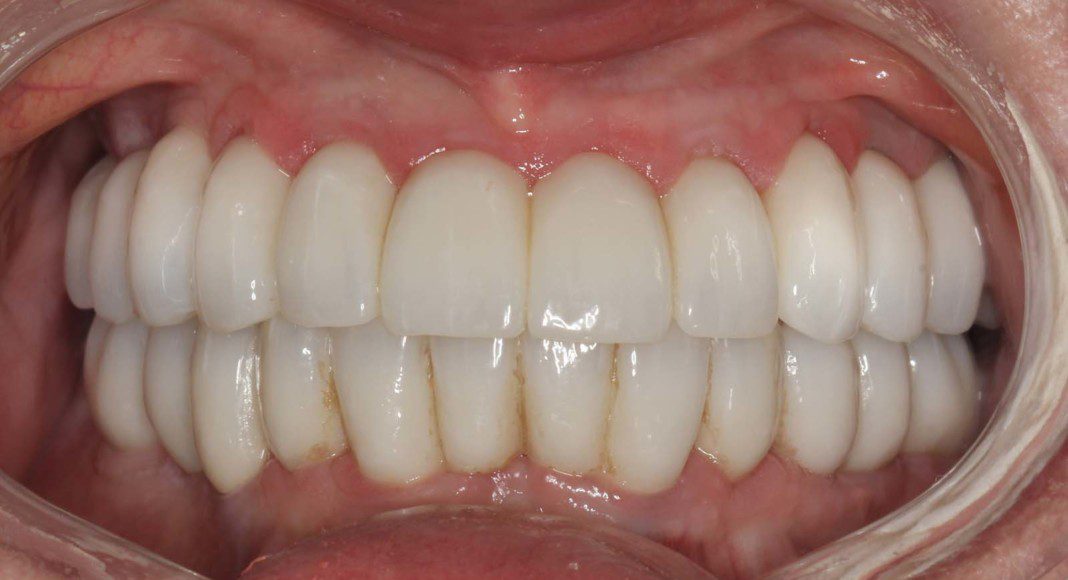

Frontal view of the implant temporary in the mouth. This temporary will stay in place for 2 more months as the bone and soft tissue remodel after the extractions.

We are now ready to begin the fabrication process of the definitive, zirconia bridges. These are the wax protypes that we use to determine tooth length, width, proper bite (lip retracted). The patient and their family members are invited to this appointment so that everyone can view the over aesthetics before we process in zirconia. Once it’s in zirconia, we cannot make big changes.

Occlusal view of the upper arch. Note: The tissues are a little red. Many patients, especially women have a slight allergy to the acrylic of the temporary bridges. This resolves after the zirconia bridge is placed.

Occlusal view of the lower arch. Note: The tissues are a little red. Many patients, especially women have a slight allergy to the acrylic of the temporary bridges. This resolves after the zirconia bridge is placed.